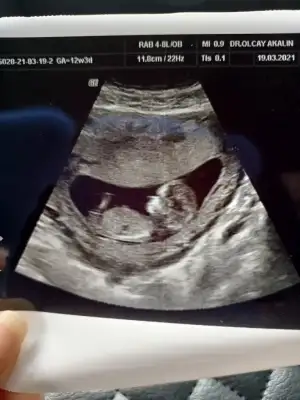

dr soylemeden siz gorun genital nub teorisi ( bebegin cinsiyeti)

Canım 2 hafta önce doktor 11 haftalıkken erkek dedi 13 hafta başka doktora gittim oda bu hafta belli olmz ama aynı senn yöntemle paralel dedi kıza benziyor dedi yani nub yöntemini kullndı kime inannacagımı şaşırdım paraleldi gerçekten 13. Hafta da 11 dede dikti canım hangisi yanılıyor bilmiyorum